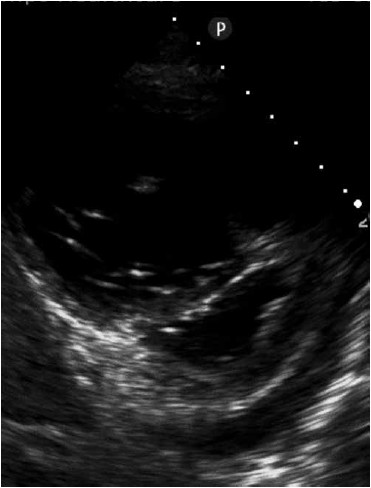

Paciente se apresenta no setor de emergência de hospital com dispneia em repouso. Ao realizar ecocardiografia direcionada, é encontrada a imagem a seguir, a qual sugere

(Arquivo pessoal; imagem usada com autorização)